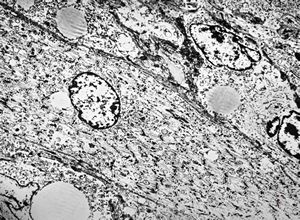

M,2m. | hypotonic syndrome - muscular atrophy